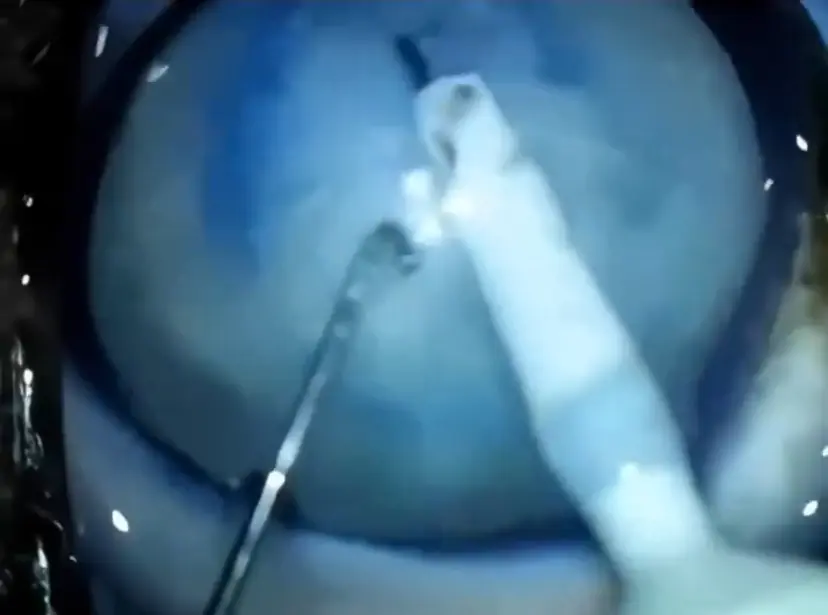

Nas imagens, o cão aparece inicialmente com os olhos turvos, um dos sintomas da catarata. Ele caminha por um corredor de hospital veterinário e, desorientado, bate o focinho nas paredes enquanto tenta reconhecer o local.

Em seguida, o vídeo mostra o procedimento cirúrgico. Em casos de cachorros idosos, os veterinários removem o cristalino opaco e o substituem por uma lente artificial. O tratamento é realizado por especialistas e costuma trazer melhora significativa na qualidade de vida do animal.